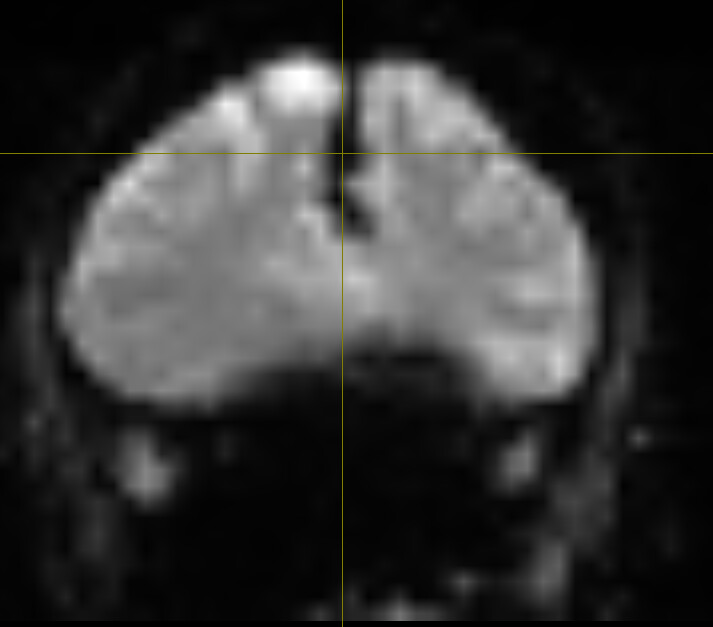

Which appears as a signal-void region, affecting LR_epi (one top) and RL_bold (two bottom) differently: